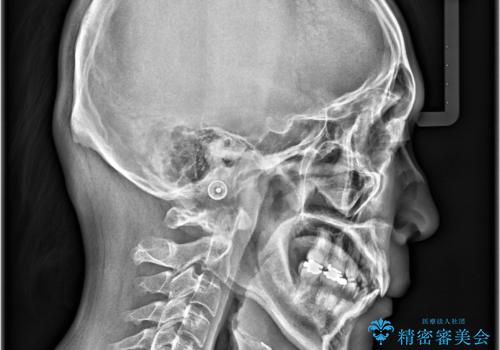

正面から見たときに右上2が全く見えないくらい、右上2が後ろに引っ込んでいる状態でしたが綺麗に並べる事が出来ました。

笑った時のスマイルラインもかなり綺麗になり大変ご満足いただく事が出来ました。

スムーズに治療を進める事ができ、2年2か月で治療をお終えました。

顔貌に対して歯の正中も合いました。